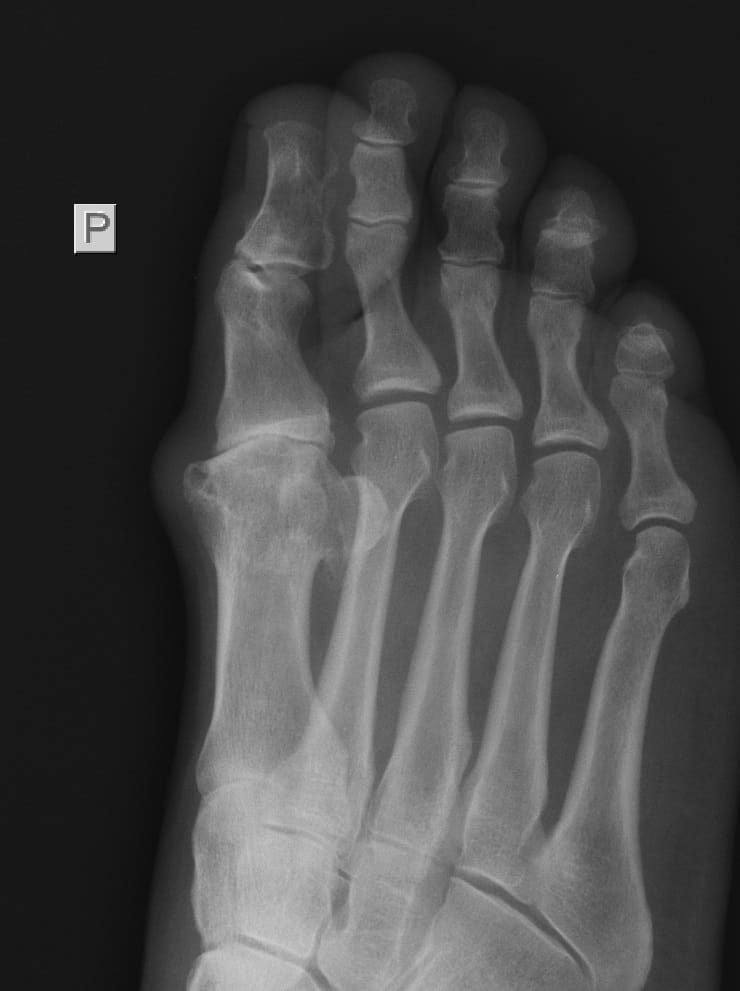

Leczenie operacyjne palucha koślawego (Halluxa)_8